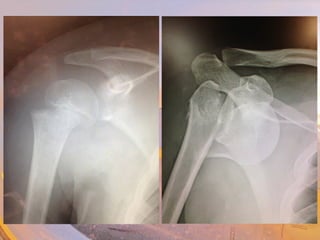

TThhee UUppppeerr EExxttrreemmiittyy

UUppppeerr AArrmm -- BBoonnee

• Humerus

– Trochlea & capitulum

– Lateral & medial

epicondyles

– Coronoid & olecranon

fossas

–Greater & lesser tubercles

– Head